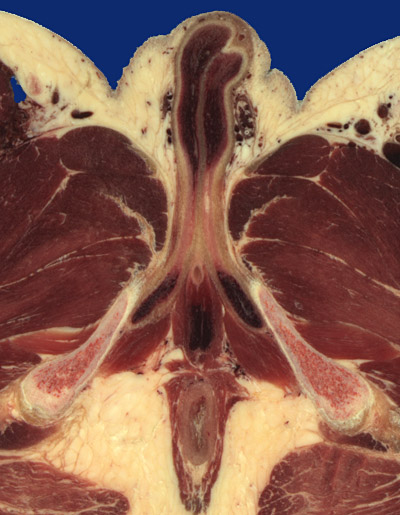

Identify the following regions in the image above: Corpus cavernosum - Cremaster m. - Pampiniform plexus - Ductus deferens - Corpus cavernosum (crus of penis) - Corpus spongiosum (bulb of penis) - Bulbospongiosus - Ischiocavernosus - Cavernous urethra - Gracilis - Ischial tuberosity - Anal canal - Levator ani (Pubo/iliococcygeus m.) - Ischioanal (ischiorectal) fossa